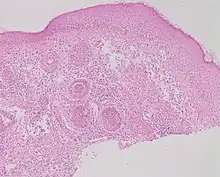

Studies of rosacea and Demodex mites have revealed that some people with rosacea have increased numbers of the mite,[13] especially those with steroid-induced rosacea. Demodex folliculitis (demodicidosis, also known as "mange" in animals) is a condition that may have a "rosacea-like" appearance.[16]

A 2007, National Rosacea Society-funded study demonstrated that Demodex folliculorum mites may be a cause or exacerbating factor in rosacea.[17] The researchers identified Bacillus oleronius as a distinct bacterium associated with Demodex mites. When analyzing blood samples using a peripheral blood mononuclear cell proliferation assay, they discovered that B. oleronius stimulated an immune system response in 79 percent of 22 patients with subtype 2 (papulopustular) rosacea, compared with only 29% of 17 subjects without the disorder. They concluded, "The immune response results in inflammation, as evident in the papules (bumps) and pustules (pimples) of subtype 2 rosacea. This suggests that the B. oleronius bacteria found in the mites could be responsible for the inflammation associated with the condition."[17]